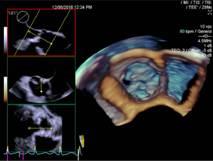

患者袁先生,有心脏二尖瓣及主动脉瓣杂音。心血管内科医生怀疑二尖瓣和主动脉瓣瓣膜病。12月5日早上,在超声室行局部麻醉下经食道四维超声心动图检查,清晰显示主动脉瓣重度狭窄,钙化呈功能二叶,排除了二尖瓣瓣膜病变,给临床提供了依据。